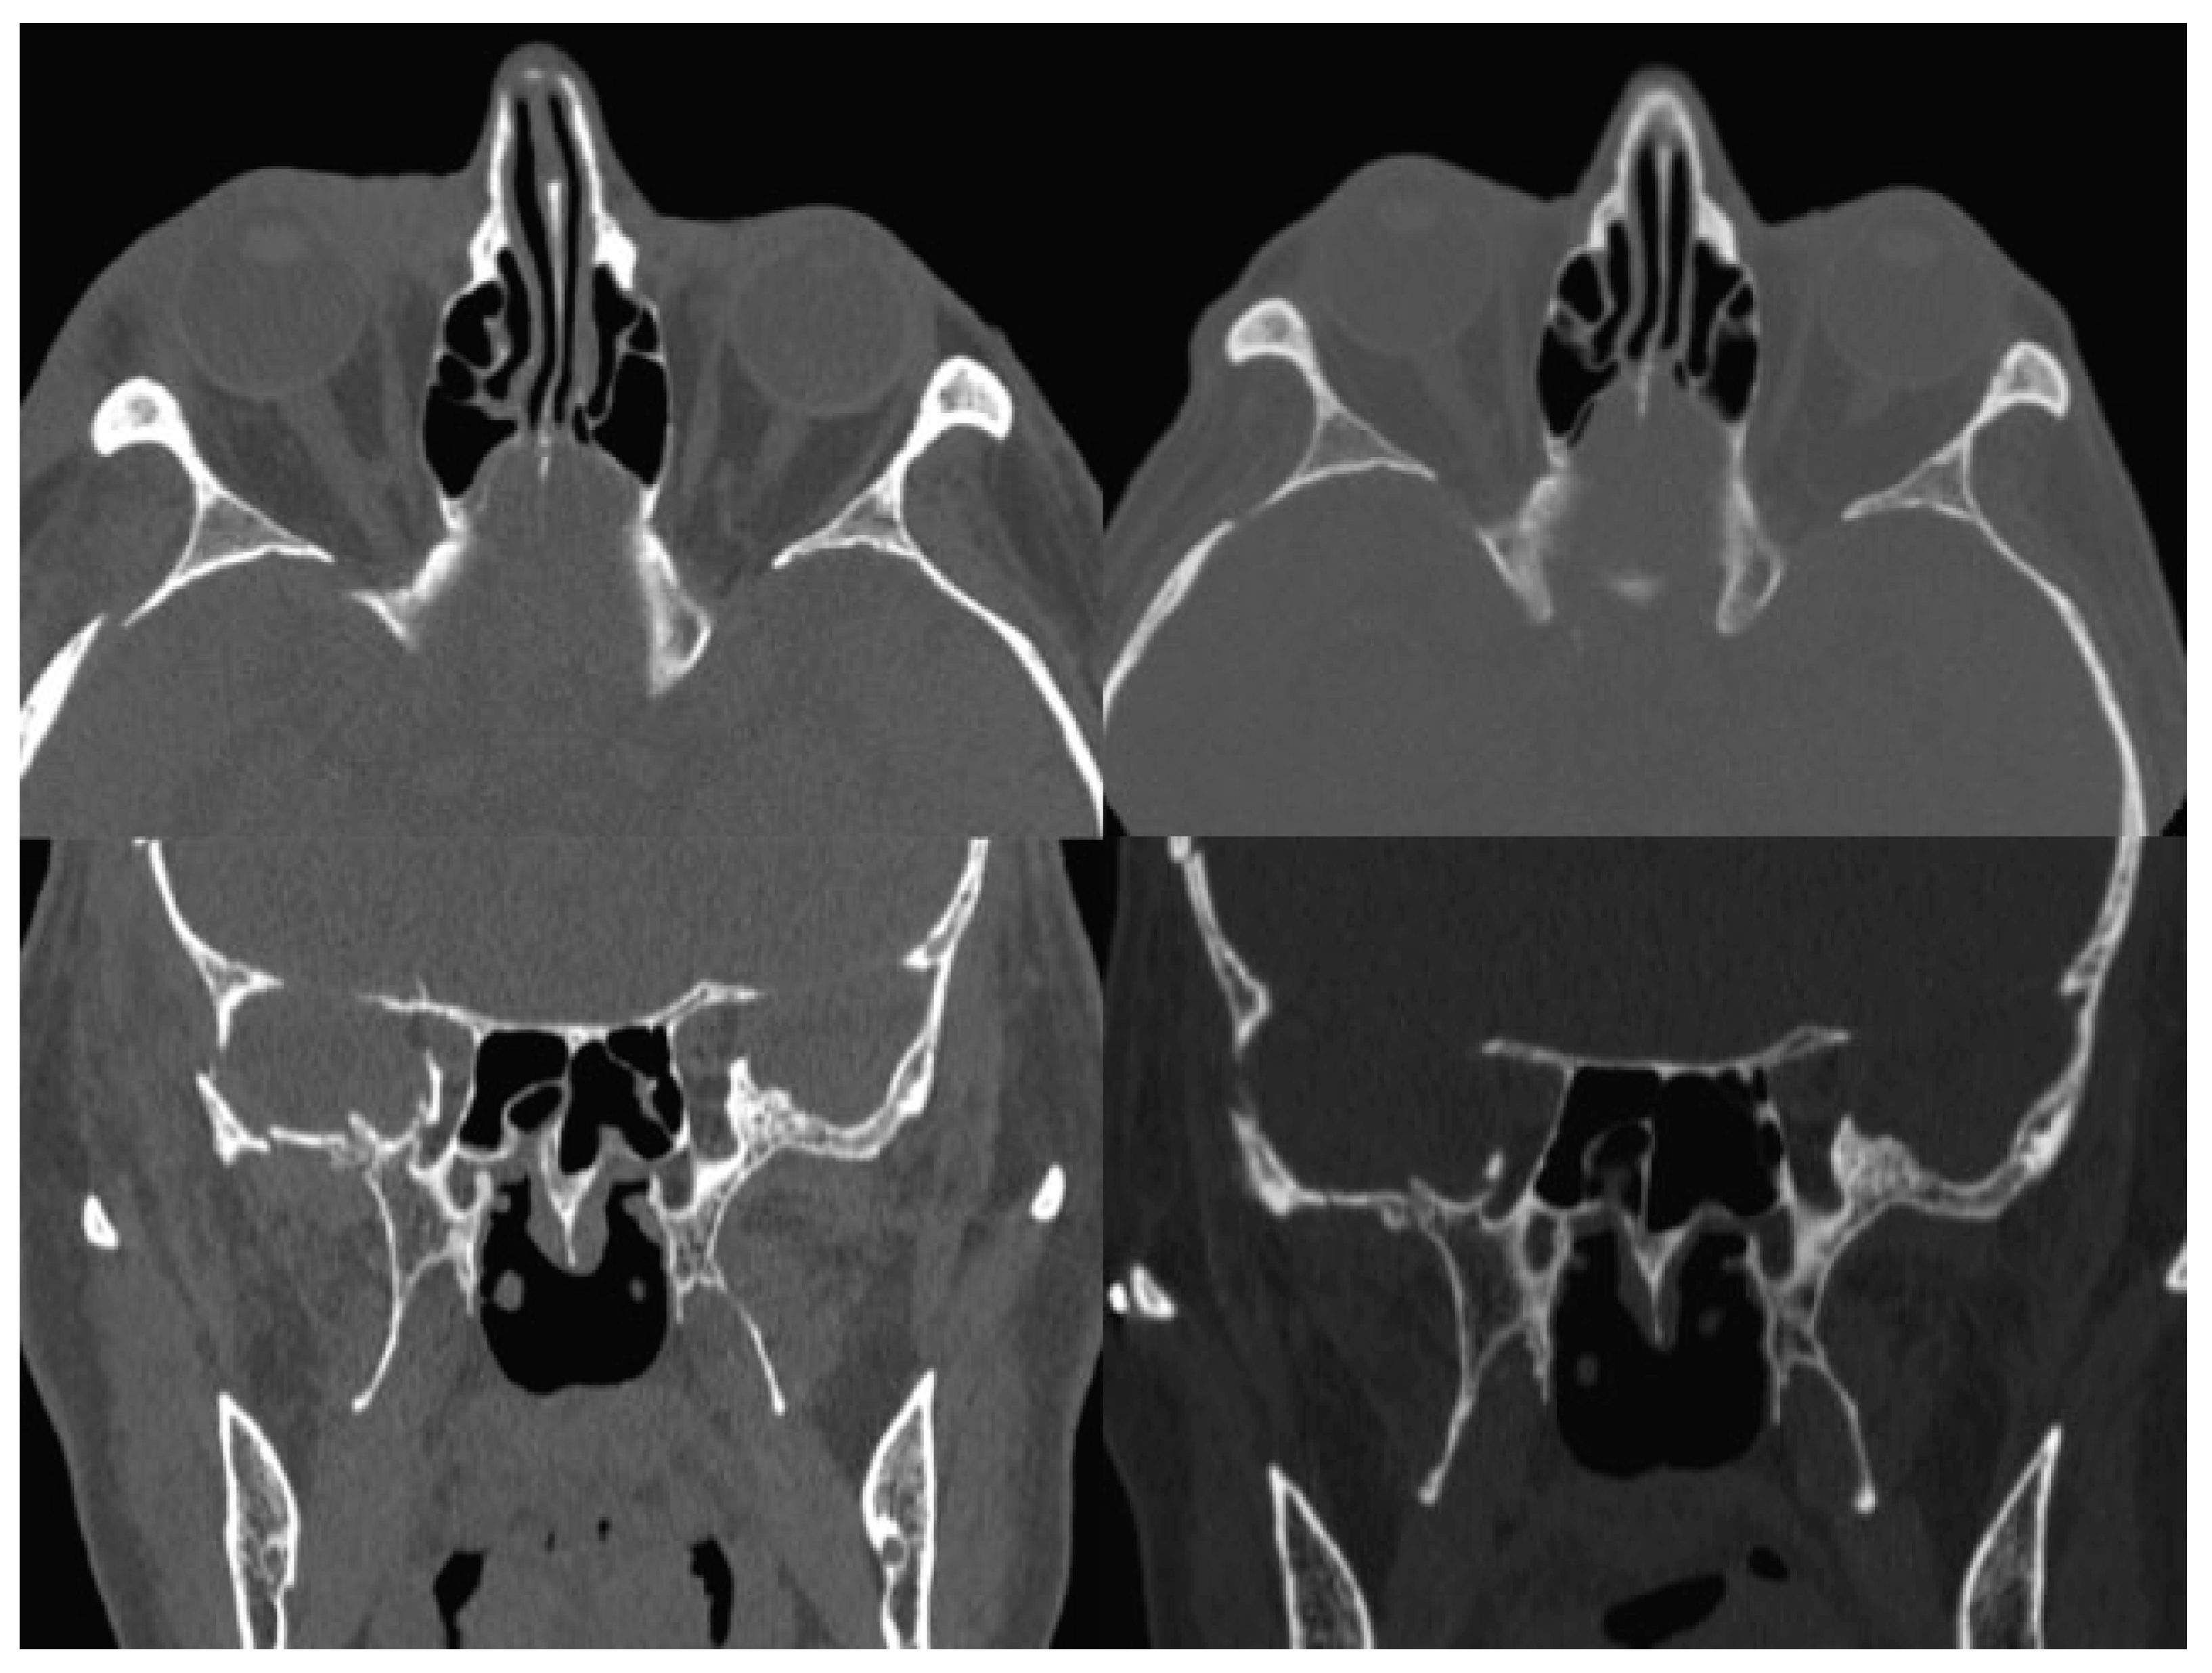

The postsurgical CT scan revealed a full recovery of the right SOF size (Figure 4). One week postoperatively, physical examination showed a great improvement of all symptoms, a prompt and almost complete recovery of the abducens movement, without diplopia (Figure 1). In 1 month, the patient completely healed.

In our case, the spiral CT scan permitted to identify a size reduction of the ipsilateral SOF and a contralateral type B fissure. The associated clinical presentation of right ptosis and complete absence of ocular movements in the right eye led to the diagnosis of right SOFS, with a traumatic physio-pathological mechanism. The VI nerve was the most severely injured.

Figure 4. Left: Axial and coronal preoperative CT scan: note SOF size reduction; right: Axial and coronal postoperative CT scan: note SOF size recovery. CT, computed tomography; SOF, superior orbital fissure.